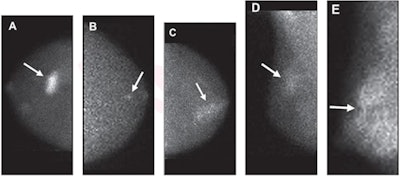

Molecular breast images show (A) mass (arrow) with marked intensity of uptake; (B) nonmass uptake (arrow) with focal distribution and mild intensity of uptake; (C) nonmass uptake (arrow) with segmental distribution and moderate intensity of uptake; (D) nonmass uptake (arrow) with regional distribution and mild intensity of uptake; and (E) nonmass uptake (arrow) with diffuse distribution and marked intensity of uptake. Image courtesy of the American Journal of Roentgenology.They looked at retrospective data from 643 lesions in 509 patients, collected between 2005 and 2017. The lesions had BI-RADS analogous categories of 0, 3, 4, or 5. Out of the total, 479 lesions were found to be benign and the other 164 malignant. Also out of the total, 83 were categorized as masses while the remaining 560 had nonmass uptake.